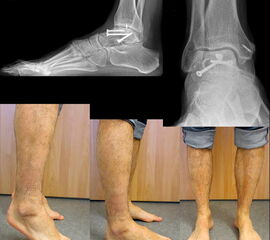

Aufgrund des vulnerablen Weichteilmantels im Bereich des Sprunggelenks weisen dislozierte zentrale Talusfrakturen (Korpus, Hals) häufig Störungen der Hauttrophik auf. Dislokationen sind meist augenfällig (Abb. 2) und die dislozierten Fragmente lassen sich perkutan tasten. Zudem ist meist eine abnorme Fußfehlstellung bei Luxationsmechanismen erkennbar. Hier ist insbesondere bei Fragmentdruck auf die periphere Durchblutung zu achten. Eine initiale Dopplersonografie oder die Indikation zur Kompartmentdruckmessung sollte durchgeführt werden.

Bei peripheren Talusfrakturen werden meist die Beschwerden im Verlauf der Bandstrukturen angegeben 14. Sie werden nicht selten übersehen, weswegen insbesondere nach der Reposition von geschlossenen subtalaren Luxationen die Indikation zur weiterführenden Diagnostik – in diesem Falle der CT – großzügig gestellt werden sollte 7.